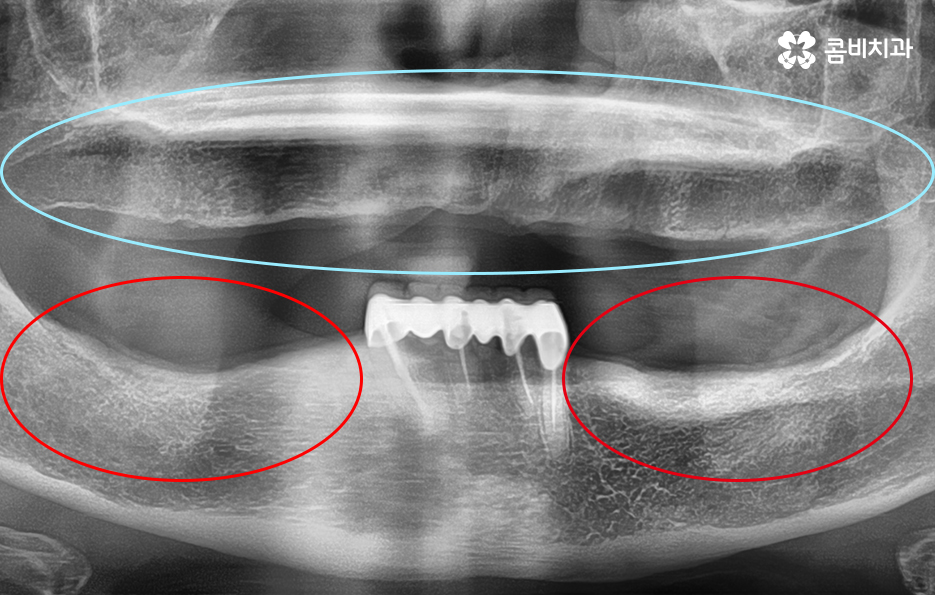

아랫니는 잇몸이 주저 앉은 상태이며 위의 잇몸과 잇몸뼈의 상태는 비교적 양호한 편

하지만 나이가 들수록 한국인들이 겪기 쉬운 당뇨나 고혈압과

같은 전신질환이 있는 경우도 있겠고 위 이미지 사례와 같이

잇몸 상태가 좋지 않은 경우도 있기 때문에 시술 과정에

있어서 개인차가 클 수 있다는 점을 미리 알아두셔야 합니다.